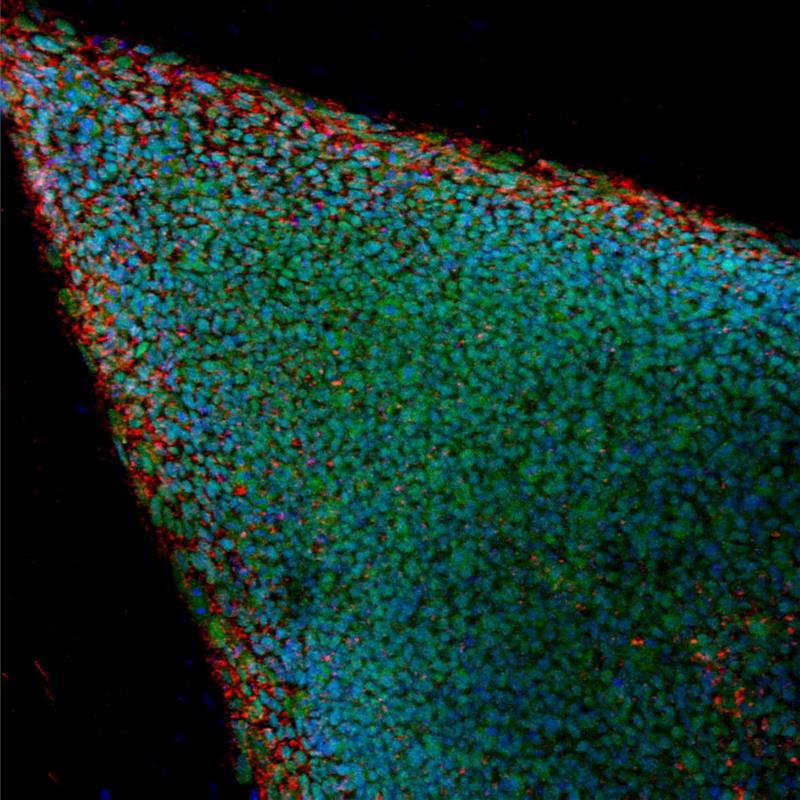

Según el instituto catalán, a través de esta técnica se ha demostrado que las zonas con heridas, que no tienen el apoyo de una matriz extracelular y que no son propicias para la adhesión celular, son alcanzadas por «puentes» multicelulares formados por láminas de queratinocitos.

De este modo, las células migratorias de la piel son capaces de continuar su avance como unidad y grupo homogéneo, para formar una barrera protectora encima de la herida.

El estudio, liderado por Lim Chwee Teck y Benoit Ladoux, de Singapur, demuestra que esta lámina de células suspendidas se propulsa gracias a fuerzas generadas por un sistema de actina y miosina, un tipo de proteínas motoras que puede causar la contracción celular.

Los investigadores han descubierto que la lámina tiene un comportamiento elástico en lugar del comportamiento fluido más característico de otros tipos celulares, lo que de alguna manera explica su habilidad para formar puentes colgantes multicelulares.